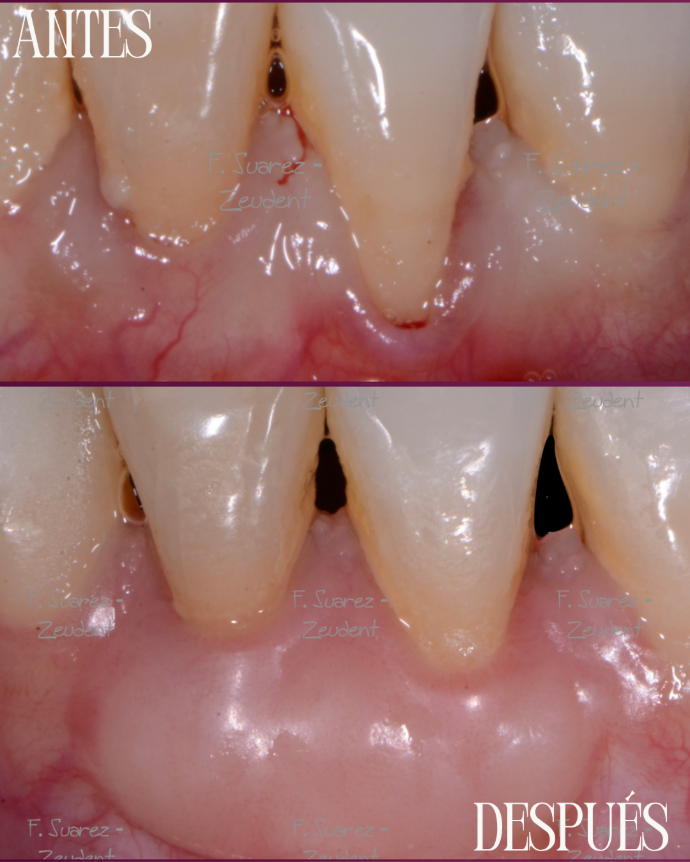

Injerto de encía

Corrige la retracción gingival y protege tus dientes, mejorando la salud y estética de tu sonrisa con un tratamiento seguro y personalizado.